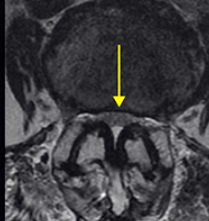

척추협착증 진단

척추협착증 진단, CT와 MRI 촬영 등을 통해서 척추관 크기와 주변 관절과 인대, 추간판의 상태를 알아보고 종합적으로 진단을 하게 됩니다. 근전도 검사와 신경전도 검사도 함께 병행해서 하게 되겠습니다.